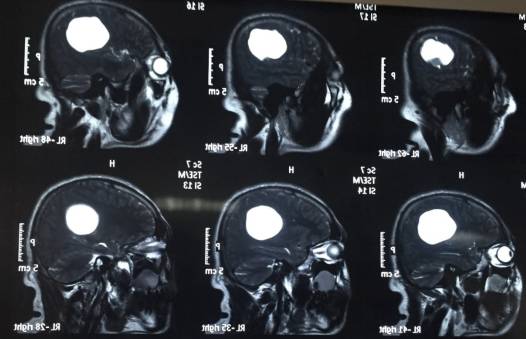

头颅MR示:右颞顶囊性占位伴结节,考虑胶质瘤可能。MRI T1为等信号(图1);T2囊液为高信号(图2);结节为均匀增强(图3);弥散相显示弥散受限(图4)。

图1. MRI T1为等信号。

图2. T2囊液为高信号。

图3. 结节为均匀增强。

图4. 弥散相显示弥散受限。

PXA在CT平扫时表现为低密度囊性病变,境界多较清楚;附壁结节呈稍低密度或等密度,壁结节常紧邻软脑膜;囊性区因含有蛋白或出血,在CT上为略高于脑脊液的液性密度。在MRI上T1W1囊性区呈低信号,壁结节为低或等信号,T2W1为囊性区呈高信号,壁结节为稍高信号。增强扫描可见肿瘤附壁结节明显强化,囊壁可轻度强化或不强化,囊壁强化代表囊壁为肿瘤组织,囊壁不强化说明囊壁为反应性增生的胶质细胞构成。影像学典型表现为囊性病变伴壁结节,少数呈囊实性病变,钙化少见。充分认识这些影像特征有助于提高其诊断及鉴别诊断的准确性,为临床治疗及对预后的判断提供重要的参考价值。少数PXA表现不典型,呈囊实性病变,表现为密度或信号不均匀,增强扫描呈不均匀强化。